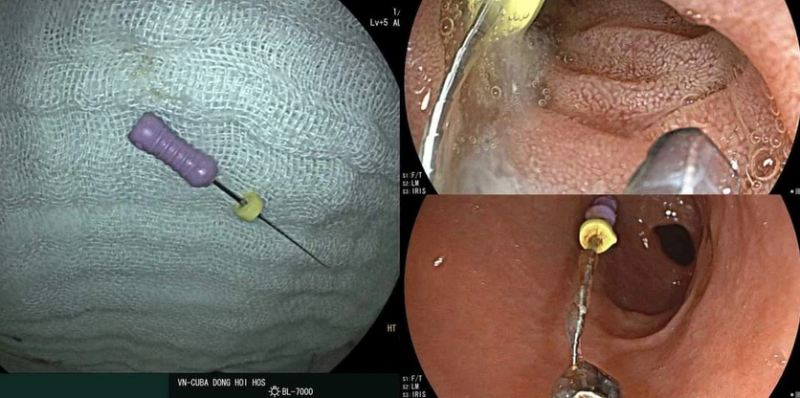

Chiều 29/1, đội ngũ y bác sĩ Bệnh viện hữu nghị Việt Nam - Cu Ba Đồng Hới, Quảng Bình đã gắp thành công cây kim nha khoa có đầu sắc nhọn kích thước khoảng 2,5cm, khi một cháu bé 5 tuổi nuốt phải.

Ngay sau khi tiếp nhận bệnh nhân, liên khoa Cấp cứu, Chẩn đoán hình ảnh, Thăm dò chức năng-Nội soi, Gây mê -Hồi sức của bệnh viện đã phối hợp tiến hành nội soi và phát hiện cây kim cháu nuốt phải và phát hiện cây kim trong ống tiêu hoá cháu H.T.T.

Quá trình nội soi, các y bác sĩ thực hiện cẩn thận, khéo léo để tránh đẩy dị vật trôi xuống sâu hơn và đã thành công gắp ra dị vật là cây kim nha khoa dài khoảng 2,5cm có đầu sắc nhọn. Hiện, sức khoẻ cháu T. đã ổn định và đang được theo dõi.